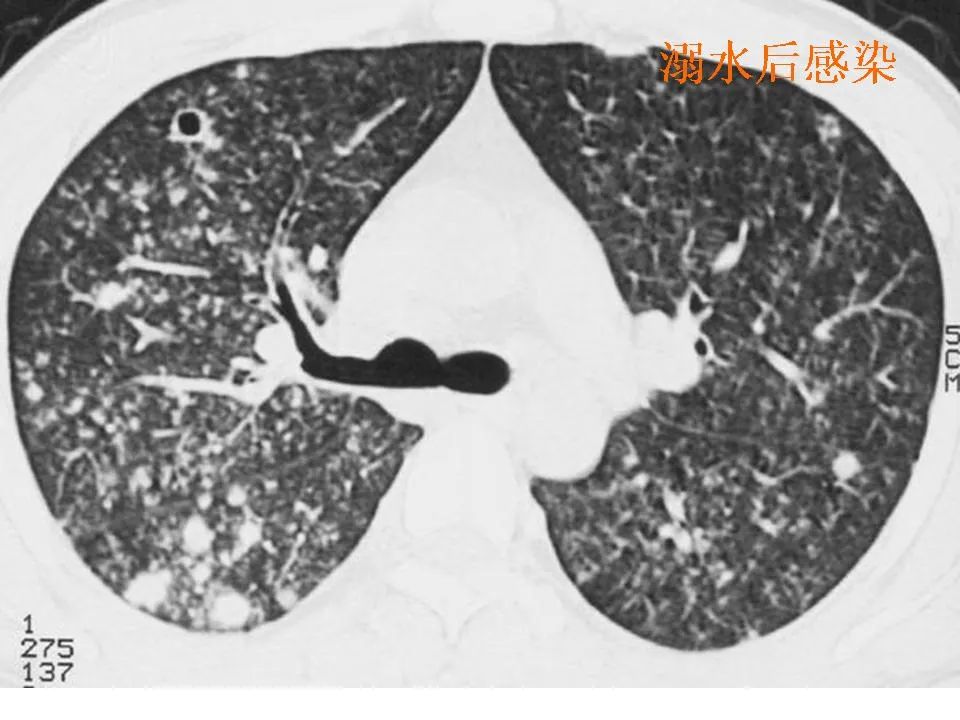

【影像读片】影像读片 肺泡细胞癌?结节病?抑或其它 [病例帖]

图片尺寸2480x1700